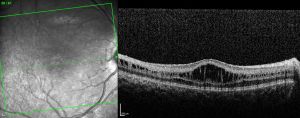

- Optical coherence tomography (OCT): usually demonstrates schisis in the superficial neural retina and thinning of the retina. In most school-aged children, there are often small cyst-like spaces peri-foveally and large cyst-like spaces within the fovea. After adolescence, the cystoid spaces may not be as evident because of flattening of these spaces with increasing age.[3] These cystoid spaces occur predominantly in the nerve fiber layer, although splitting can occur between other retinal layers as well.[10] OCT can reveal areas of schisis that may not be visible on fundus examination.